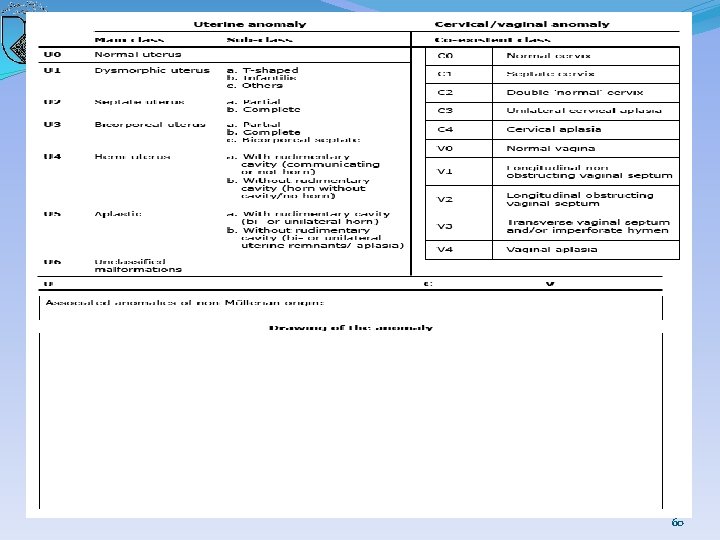

60